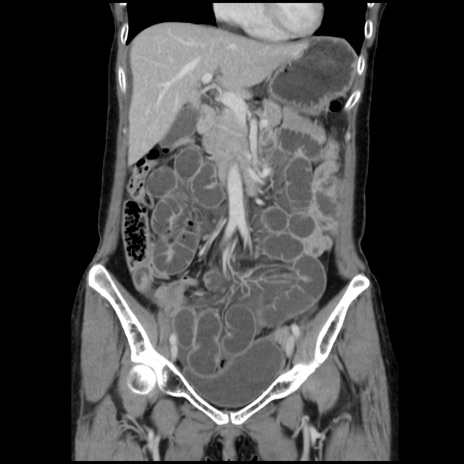

横断像

【症例】40歳代 女性

【主訴】上腹部痛、嘔気・嘔吐

【現病歴】約9時間前頃から急に上腹部痛、嘔気、嘔吐が出現。改善しないため救急要請。

【既往歴】子宮頚癌(広汎子宮全摘術、放射線療法)、腸閉塞

【身体所見】腹部:平坦、軟、腸雑音亢進、上腹部を中心に腹部全体に圧痛あり。

【データ】WBC 8400、CRP 0.03